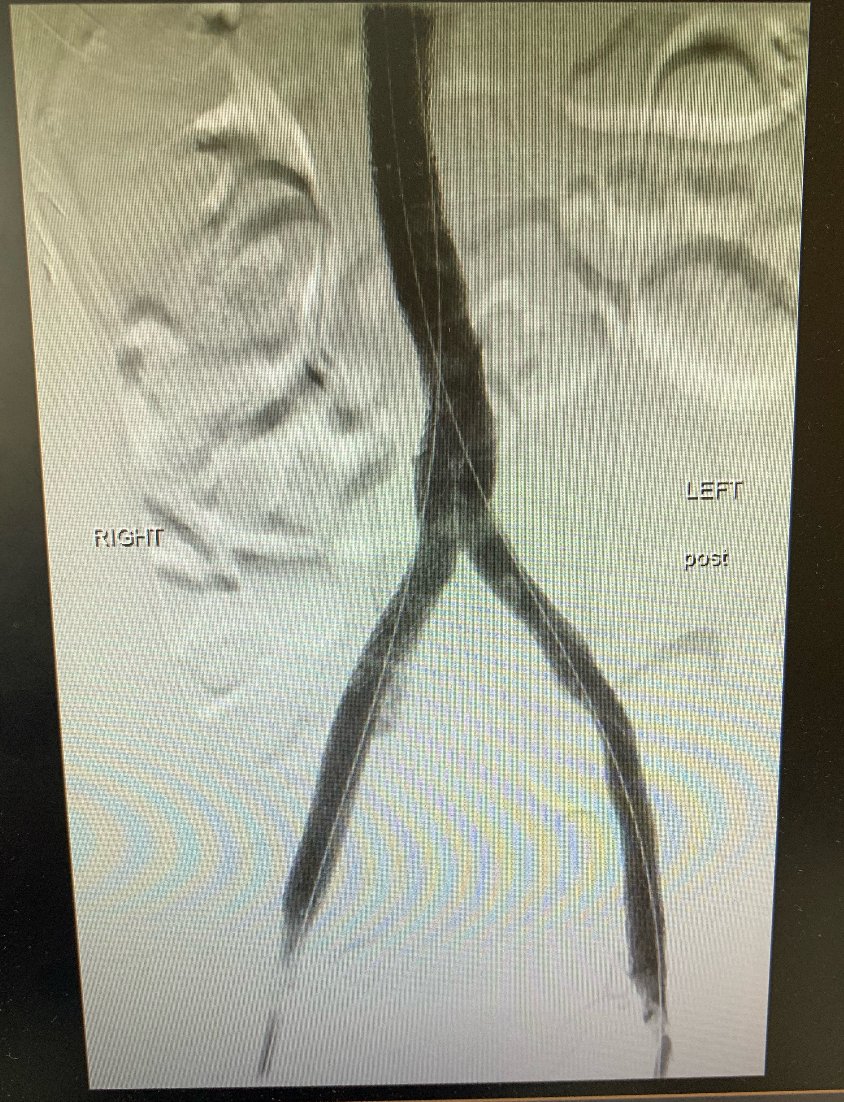

A great iliocaval reconstruction case for caval atresia. Check out the difference in the before and after! #medtwitter #veinmonday